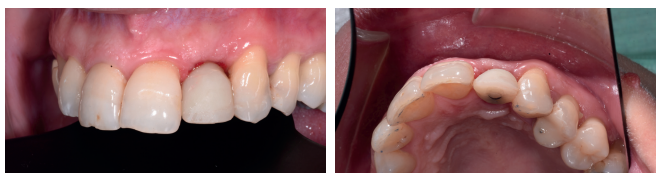

En la historia clínica, no se evidenciaron antecedentes médico-quirúrgicos de interés, alergias medicamentosas conocidas ni hábitos nocivos. A la exploración extraoral, se observó una línea de sonrisa media-baja (Figura 1). A la exploración intraoral, se apreciaron varias ausencias dentarias (1.7, 3.6 y 4.6) y un incisivo lateral superior izquierdo con una restauración fija dentosoportada (Figuras 2 y 3).

En la exploración radiográfica mediante radiografía panorámica se apreciaron los molares inferiores mesializados por la ausencia de los primeros molares inferiores (Figura 4A). En el escáner de haz cónico se evaluó el nivel de inserción del incisivo lateral superior izquierdo (Figura 4B).

verticales en zonas de molares. (B) Escáner de haz cónico, donde se aprecia el soporte óseo reducido del incisivo lateral

superior izquierdo.